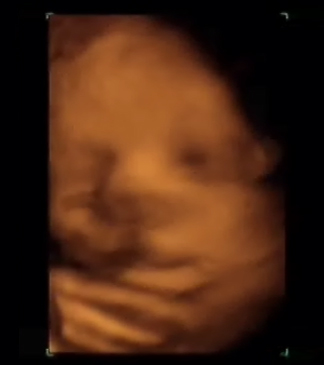

34 semanas y 3 días

35 semanas

36 semanas

Ya es muy tarde para hacer 4D pero todavía podemos conseguir con un poco de suerte, imágenes como las que están observando. En esta edad gestacional la falta de líquido, las manos delante de la cara y el cordón dificultan muchas veces la obtención de las imágenes. Si venís en esta edad gestacional, tomad 30 minutos antes un poco de azúcar.